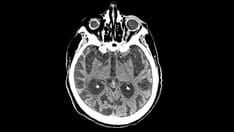

Chronic Traumatic Brain Injury Associated with Boxing

In view of the limited and proven treatment protocols for CTBI, the prevention of CTBI remains of paramount importance. The mainstay of preventing CTBI in boxing is to limit excessive exposure. This would be best accomplished by detailed medical surveillance and supervision of active boxers by the regulatory agencies (i.e., state boxing commissions), as advocated by federal legislation.[63] Boxers at high risk for CTBI (e.g., older boxers, boxers with long careers, poor performers, boxers with multiple concussions) can be identified and required to undergo more detailed neurological evaluation to determine whether they are experiencing the untoward effects of boxing. If a boxer is noted to be experiencing neurological deterioration, that boxer should be prohibited from continued participation in the sport.